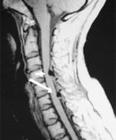

正常人的脊椎分别由颈椎、胸椎、腰椎和骶椎组成。它们借助韧带、软骨和关节连接在一起构成人体的脊柱。颈椎其实就是位于颈部的脊椎,由7块骨头联结而成。在脊椎中,颈椎体积最小,但灵活性最大、活动频率最高、负重也较大。具体说来,颈椎位于头部、胸部与上肢之间。颈椎周围包绕着血管、神经和颈部肌肉,组成脖子。

颈椎,上托头颅,下连躯体,是人体的重要支撑和神经的重要通道,还是人体劳动强度最大的枢纽关节部位。更具体地说,颈椎不仅负责支持头颅的重量,大脑发出的种种神经支配信息也是通过颈椎输送到全身各躯干的。另外,全身各躯干也通过颈椎向大脑发送各种神经信息。“结构决定功能和作用”,颈椎也不例外。其功能与作用主要取决于构成颈椎的7块颈椎骨。

前文说过,脊柱颈段由7块颈椎骨重叠连接而成。在7块颈椎骨中,第1、2、7颈椎骨因形状有所差异,有特殊颈椎之称。第3、4、5、6颈椎骨,形态基本相似,均由椎体、椎弓和突起三部分构成,称为普通颈椎。

当7块椎体叠压排列在一起时,中间有一个圆形孔道——“椎管”,负责人体神经传递的脊髓便是从这里面通过。在脊髓两侧分别有脊神经从椎间孔向左右分出,用来支配人体正常活动。